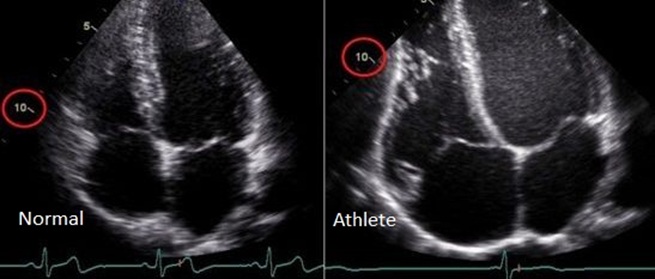

В это время изменяются стандартные показатели работы сердечных камер, которые можно измерить с помощью ЭКГ и ультразвукового исследования. Увеличиваются минутный и ударный объемы крови (количество крови, проходящей через сердце за минуту и за одно сокращение) — более 5 литров в минуту и свыше 70 мл за одно сокращение соответственно. Благодаря адаптивным механизмам частота проведения электрических импульсов по миокарду уменьшается, что проявляется в снижении частоты сердечных сокращений (около 50 ударов в минуту, в отличие от 70-80 ударов в минуту у нетренированного человека). Снижение частоты сердечных сокращений (брадикардия) при регулярных нагрузках положительно сказывается на сердечной мышце, так как при учащенном сердцебиении (что характерно для обычного человека с пульсом 100-120 в минуту после нагрузки) возникает повышенная потребность в кислороде для самой сердечной мышцы.

Спортивное сердце, или синдром сердца спортсмена, представляет собой адаптацию сердечно-сосудистой системы к высоким физическим нагрузкам. Врачи отмечают, что у профессиональных атлетов наблюдается увеличение размеров сердца, особенно левого желудочка, что может быть нормальным физиологическим процессом. Однако важно различать адаптацию и патологию. Симптомы, такие как одышка, учащенное сердцебиение или боли в груди, могут указывать на возможные проблемы. Диагностика включает ЭКГ, эхокардиографию и стресс-тесты, которые помогают выявить изменения в работе сердца. Врачи предупреждают, что игнорирование симптомов может привести к серьезным последствиям, включая риск аритмий и сердечной недостаточности. Регулярные медицинские осмотры и внимательное отношение к своему здоровью являются ключевыми для спортсменов.

Для определения наличия спортивного сердца каждому атлету рекомендуется проходить ультразвуковое исследование сердца (эхокардиоскопию, Эхо-КС) не реже одного раза в год. Этот метод позволяет точно оценить объем сердца, ударный объем крови, размеры предсердий и желудочков, а также толщину стенок миокарда. Если полученные данные значительно превышают норму, спортивный врач должен рассмотреть возможность снижения интенсивности тренировок или их прекращения. Также для оценки состояния сердечной мышцы полезен Гарвардский степ-тест, основанный на подсчете частоты сердечных сокращений после физической нагрузки.